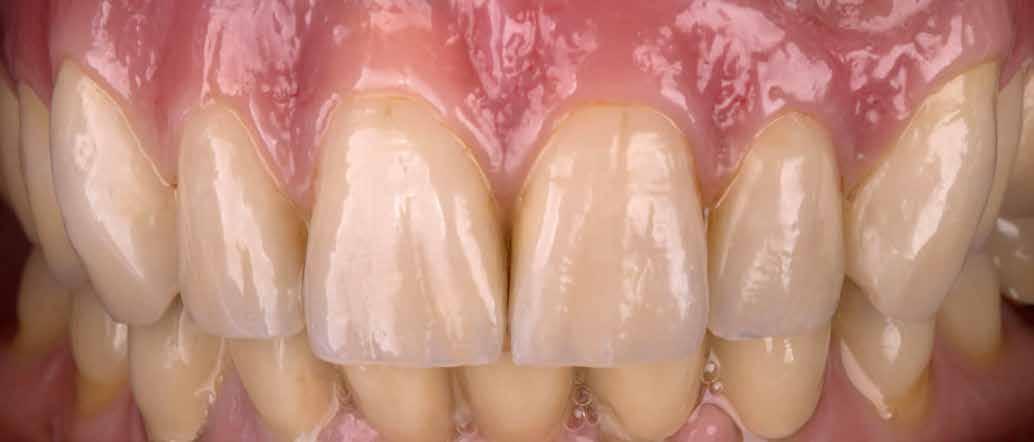

Interdiszciplináris fogászati kezelés myofunkcionális készülék, alignerek és protetikai ellátás alkalmazásával

MED. DENT Abradált frontfogakkal rendelkező felnőtt páciens interdiszciplináris kezelése